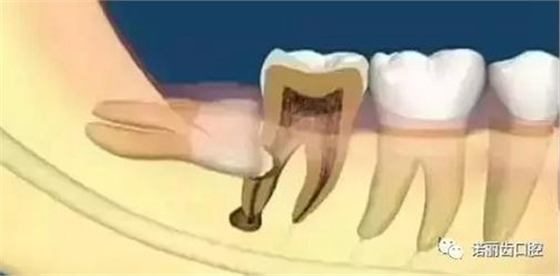

阻生智齒

這是比較常見(jiàn)的一種問(wèn)題,該種智齒通常埋在齒槽骨的里面,如果經(jīng)常發(fā)生炎癥,或是診斷會(huì)有病灶發(fā)生的時(shí)候,就必須拔除。